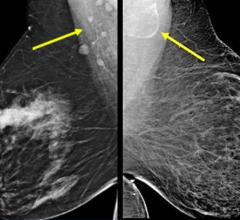

Despite decades of progress in breast imaging, one challenge continues to test even the most skilled radiologists ...